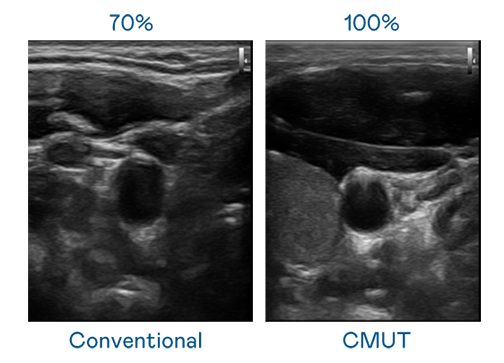

CMUT 技術是一種用電容式微機電元件來產生超音波訊號的技術。與傳統 PZT 壓電式技術相比,CMUT 頻寬增加 30%,更寬頻的超音波訊號讓影像解析度大幅提升,是實現高影像品質醫療超音波掃描、促進精準醫療發展的關鍵技術。

大頻寬帶來超清晰影像

超音波影像的解析度高低,首先取決於探頭能發出的訊號頻寬。乐竞官网登录入口 CMUT 可提供高清晰的超音波訊號,提供高頻寬、高靈敏度、影像紋理細節更高的超音波影像,協助醫護人員縮短影像判讀時間及利用精準的醫療影像進行診斷。